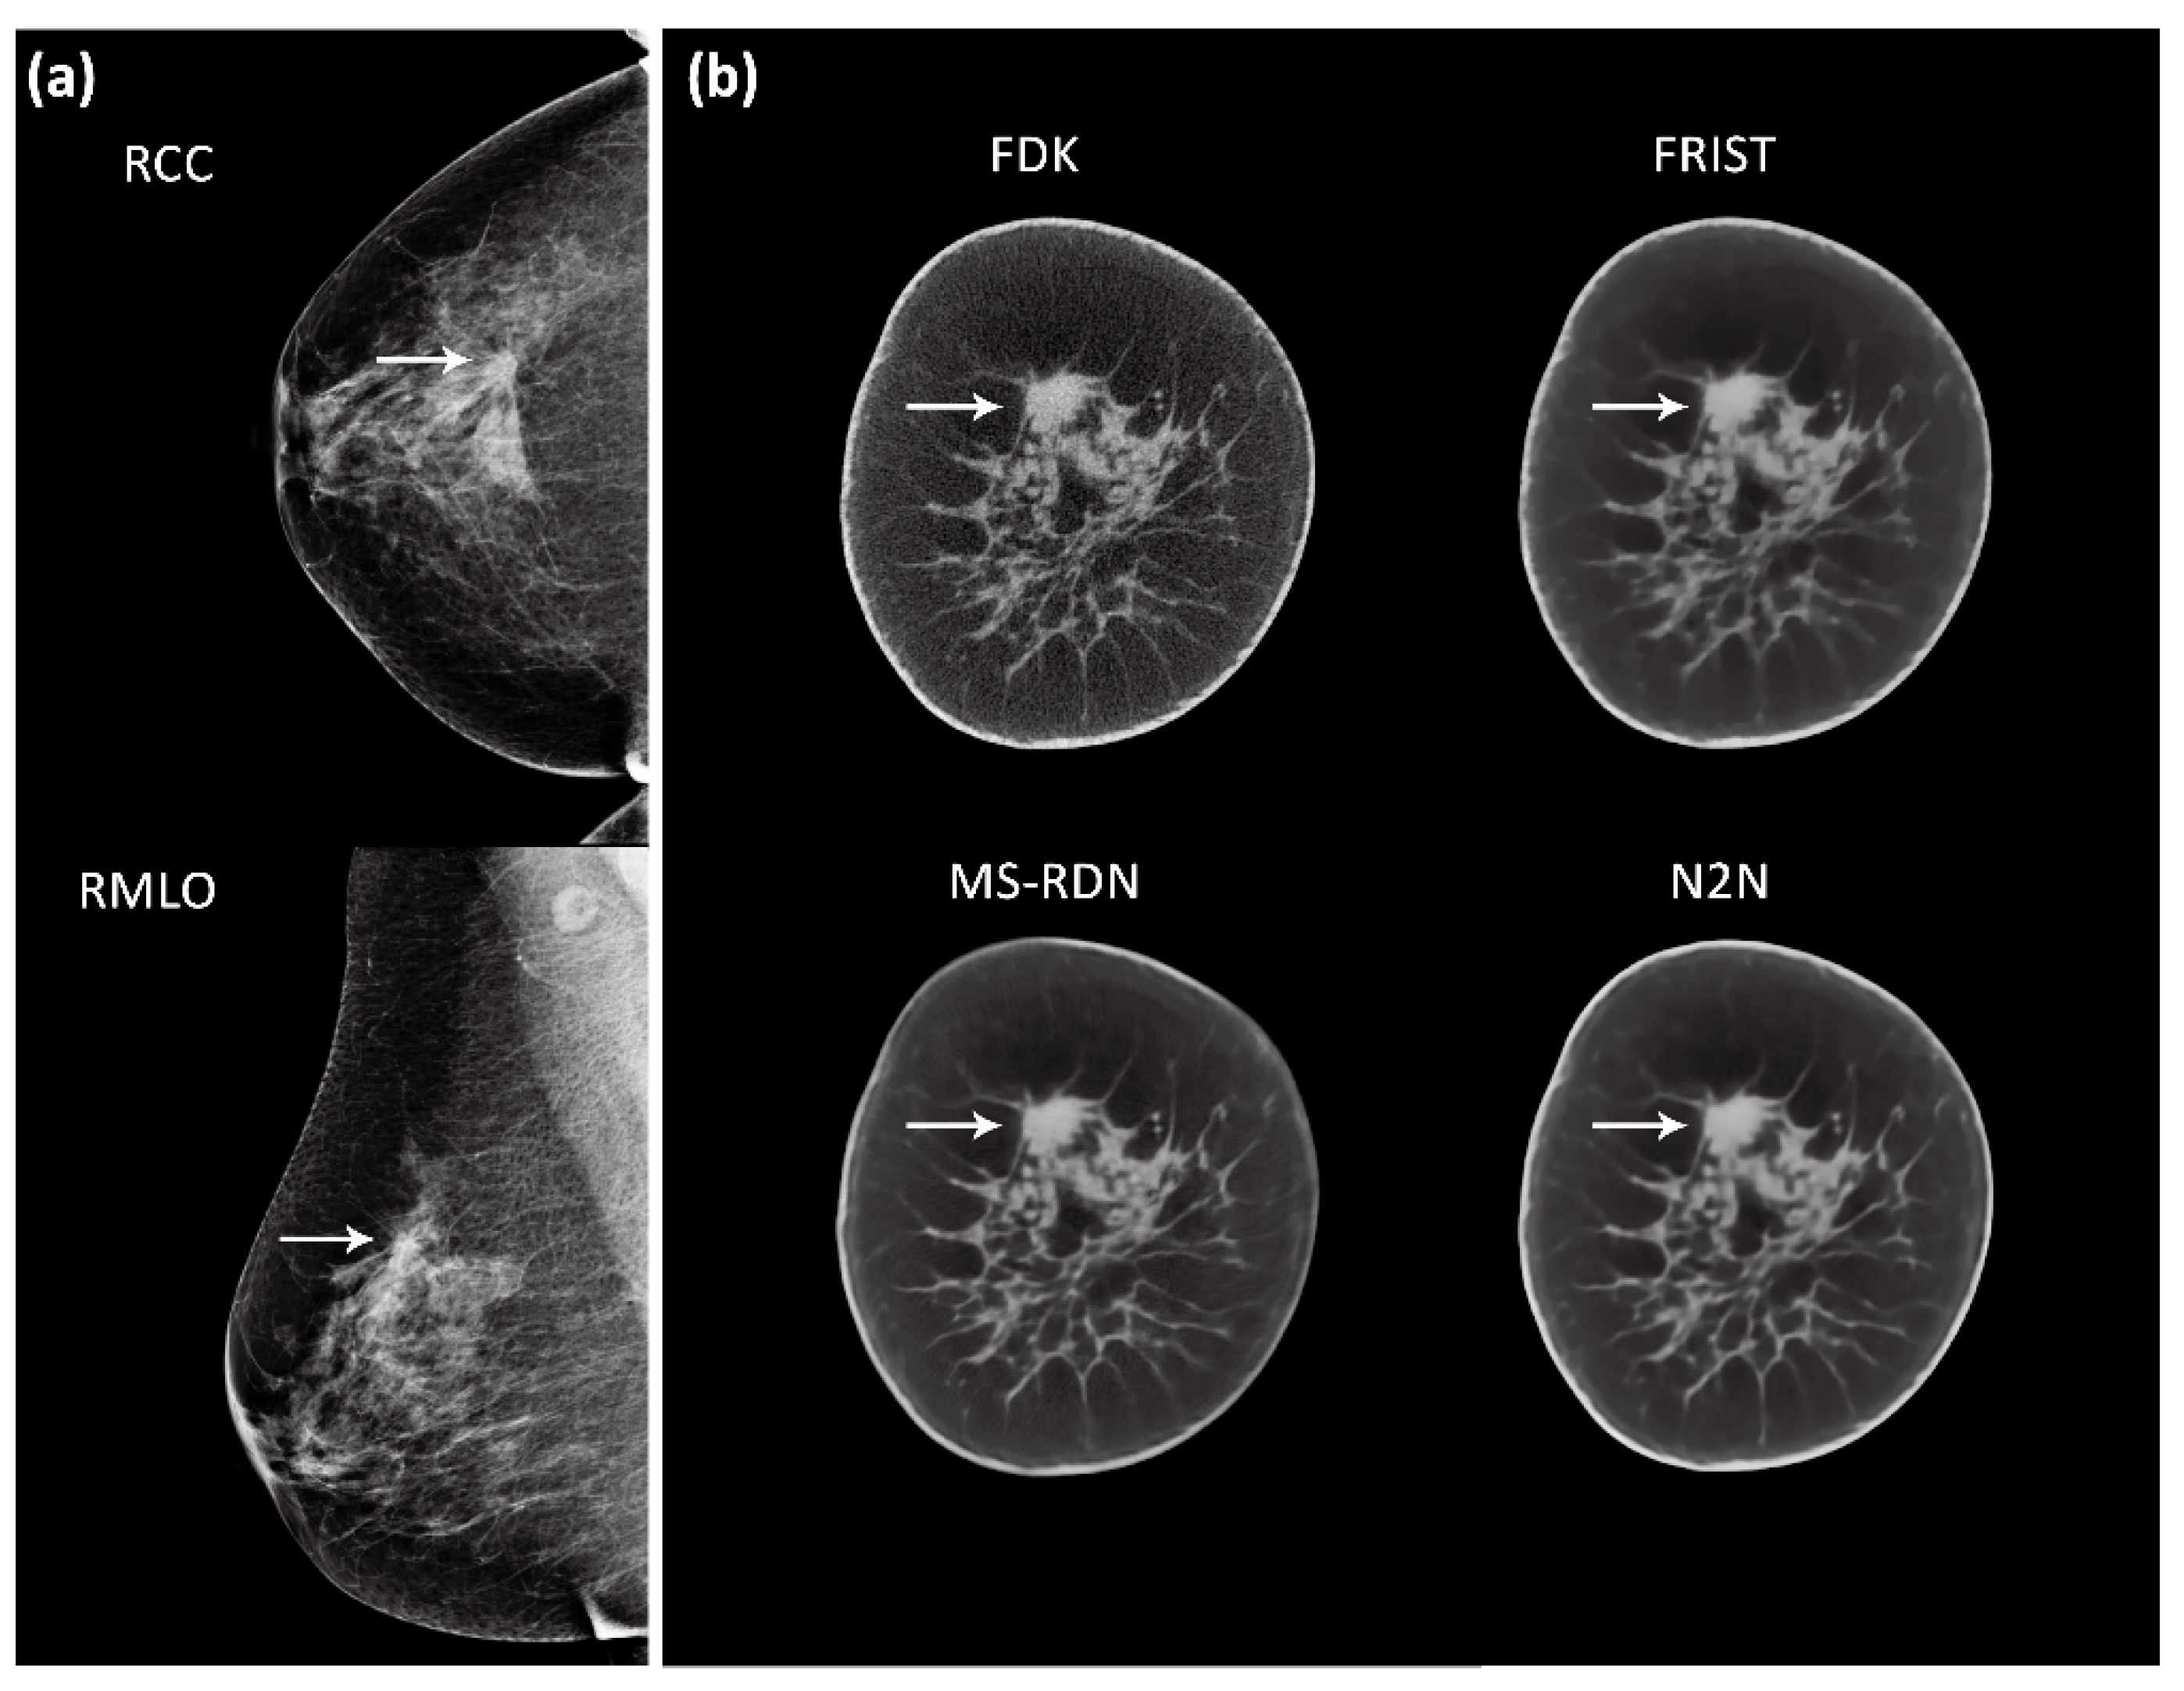

- Fu, Z.; Tseng, H.W.; Vedantham, S.; Karellas, A.; Bilgin, A. A residual dense network assisted sparse view reconstruction for breast computed tomography. Sci. Rep. 2020, 10, 21111. [Google Scholar] [CrossRef]